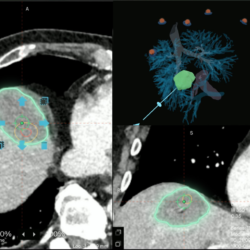

CAS-One IR to zaawansowany system wspomagający ablację guzów, który łączy planowanie zabiegów w 2D/3D, sztuczną inteligencję i śródzabiegową ocenę skuteczności.

Dzięki precyzyjnemu pozycjonowaniu igieł i zaawansowanych funkcji AblaSure możliwa jest natychmiastowa weryfikacja skuteczności ablacji, co pozwala znacznie obniżyć ryzyko progresji miejscowej guza (LTP) oraz ograniczyć powikłania.

- Planowanie i nawigacja zabiegu w 2D i 3D z wykorzystaniem wizualizacji opartych na sztucznej inteligencji

- Wizualizacja stref ablacji z użyciem ponad 75 typów igieł, niezależnie od modalności obrazowania